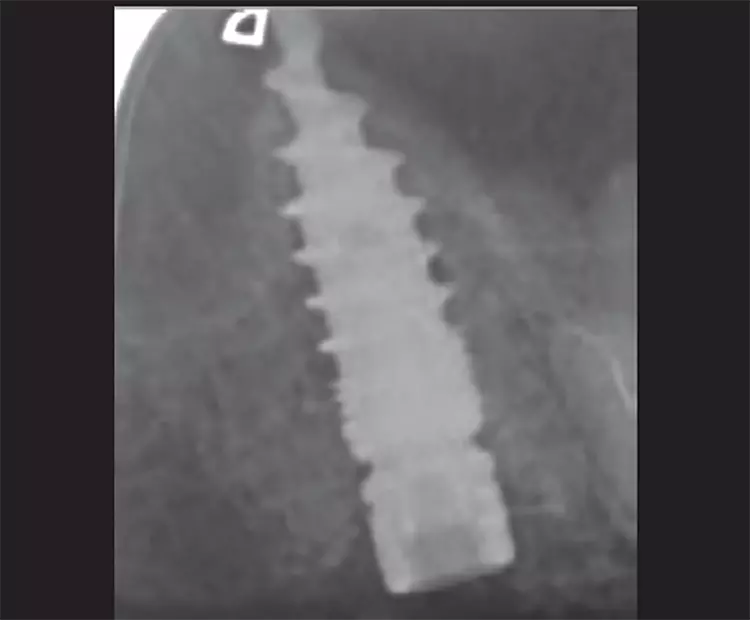

Zahn 17 konnte nicht erhalten werden. Gebohrt und mit WS-Condensern wurde im „gesunden“ Knochen im Bereich der Trikfurkation die neue Kavität zur Aufnahme eines Champions (R)Evolution L 8 mm | ø 4,0 mm mit einer finalen Primärstabilität von 40 Ncm aufbereitet (Abb. 27-29).